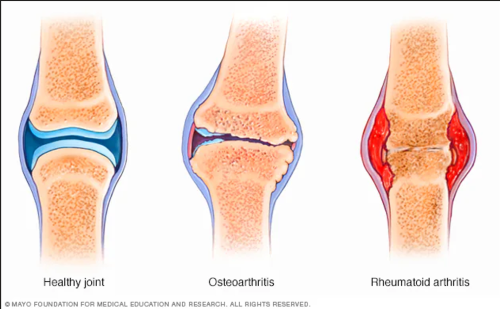

- Viêm khớp dạng thấp: là một bệnh tự miễn, khi hệ miễn dịch tấn công nhầm vào các mô khớp, gây ra viêm, đau và sưng. Nếu không được điều trị kịp thời, bệnh có thể dẫn đến biến dạng khớp và mất chức năng.

- Thoái hóa khớp: Là quá trình thoái hóa tự nhiên của sụn khớp do tuổi tác, chấn thương hoặc sử dụng quá mức. Biểu hiện chính của bệnh là đau và cứng khớp, thường gặp ở các khớp chịu lực như khớp gối, khớp hông và cột sống.